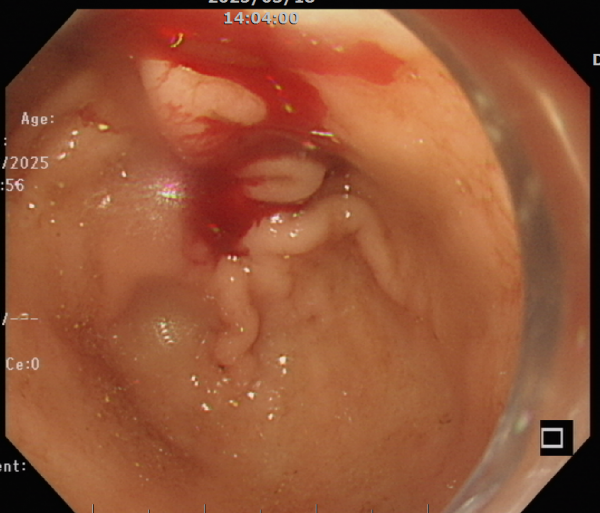

檢查時,食道與胃部乾乾淨淨,完全沒有血跡。但就在下一秒,鮮紅的血從幽門湧入胃內,立刻通過幽門進入十二指腸,發現裡面一片血紅。此時,先前在胃鏡前端裝上的透明帽發揮了關鍵作用,它能幫助推開腸道黏膜、沖水清理,讓視野更清楚。在仔細搜尋後,在十二指腸第一部位發現出血區域,但由於出血速度太快,無法立即看到破裂的血管。

患者禁食時間足夠,立刻安排緊急胃鏡檢查。食道與胃部乾乾淨淨,完全沒有血跡。但就在下一秒,鮮紅的血從幽門湧入胃內。(圖/北榮新竹分院 提供)